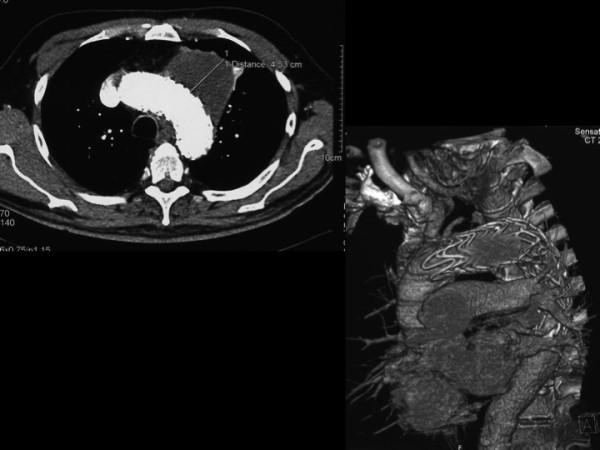

Ruptured aortic arch aneurysm is a life threatening disease. Surgical repair has an high perioperative mortality rate and totally endovascular treatment is a challenge. Hybrid repair has been proposed as a valuable approach. We report the case of a patient with a contained rupture of aortic arch aneurysm. We treated him with a debranching of supraortic vessels with carotid-carotid and carotid-subclavian bypass and deployment of two enodgrafts in two different times. We consider hybrid treatment for arch and hemiarch a feasible option for aortic arch aneurysms in non emergent and in an emergency setting with an improvement in perioperative morbidity and mortality.

主动脉弓动脉瘤破裂是一种危及生命的疾病。手术修复围手术期死亡率高,完全血管内治疗具有挑战性。杂交修复已被提出作为一种有价值的方法。我们报告一例主动脉弓动脉瘤局限性破裂患者的病例。我们通过颈动脉-颈动脉和颈动脉-锁骨下动脉旁路对主动脉上血管进行去分支,并分两次植入两枚血管内移植物对其进行治疗。我们认为,对于非急诊和急诊情况下的主动脉弓动脉瘤,杂交治疗主动脉弓和半弓是一种可行的选择,可改善围手术期发病率和死亡率。